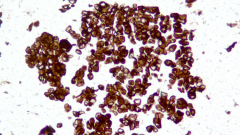

| Description | CLDN18.2是Claudin蛋白質(zhì)家族的一員,位于細胞膜表面,Claudin18.2(CLDN18.2)表達具有特異性。其作為Claudins蛋白的一個亞型,在正常組織中僅表達于分化的胃黏膜上皮細胞。在胃癌、食管癌和胰腺癌等多種腫瘤中表達,并且不僅限于原發(fā)病灶,在轉(zhuǎn)移灶中也有表達。目前臨床研究中使用的檢測方法均為免疫組化。 |

| 示例 | ![]() |

| IHC染色結果 | |